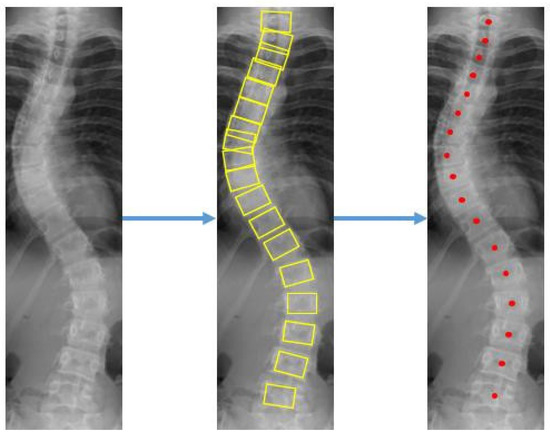

Precise surveillance and assessment of spinal disorders are important for improving health care and patient survival rates. The assessment of spinal disorders, such as scoliosis assessment, depends heavily on precise vertebra landmark localization. However, existing methods usually search for only a handful of keypoints in a high-resolution image. In this paper, we propose the S2D-VLI VLDet network, a unified end-to-end vertebra landmark detection network for the assessment of scoliosis. The proposed network considers the spatially relevant information both from inside and between vertebrae. The new vertebral line interpolation method converts the training labels from sparse to dense, which can improve the network learning process and method performance. In addition, through the combined use of the Cartesian and polar coordinate systems in our method, the symmetric mean absolute percentage error (SMAPE) in scoliosis assessment can be reduced substantially. Specifically, as shown in the experiments, the SMAPE value decreases from 9.82 to 8.28. The experimental results indicate that our proposed approach is beneficial for estimating the Cobb angle and identifying landmarks in X-ray scans with low contrast. Full article

Figure 1